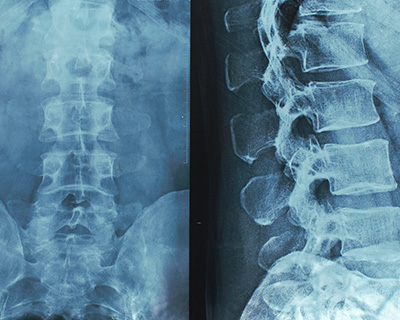

脊椎外科は、整形外科の分野のなかでも、高度な技術と専門性を要求される分野です。主として背骨(脊椎)および背骨の中を通る神経(脊髄)の疾患、外傷、腫瘍を取り扱います。

しずおか整形外科病院では、高画質・高速な撮影が可能な検査機器を取り入れております。また、高速な撮影により、検査時間の短縮や低被曝により患者様の負担を大幅に減らし、安心して検査を受けることができます。

短い時間で、体の中をくわしく撮影し、最先端の技術による被曝削減により安全に調べられる検査装置。